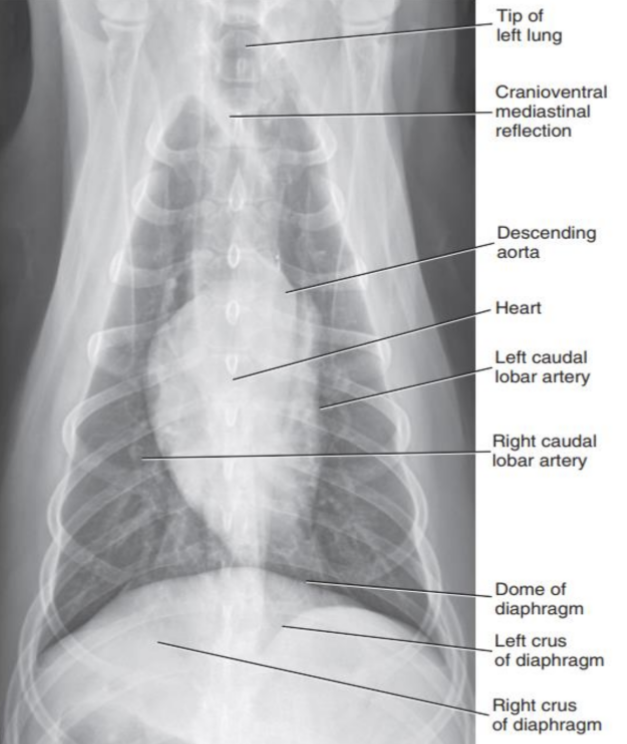

1. Normal Anatomy

| Thorax | |